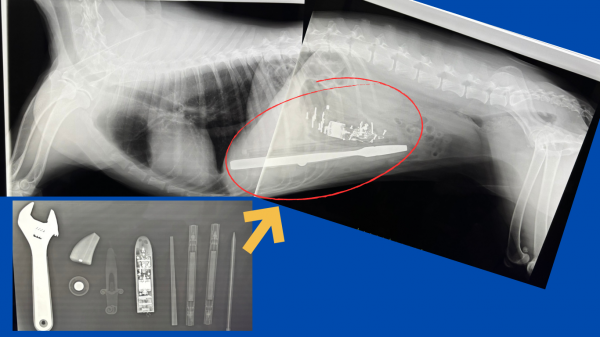

レントゲンの写真は実際僕が過去に手術したゴールデンレトリバーの異物摘出の子のレントゲンです。

この子はレンチ、新幹線のおもちゃ、ボールペンなど色々なもの食べてしまっていました。

全て手術にて摘出して、無事退院しています。